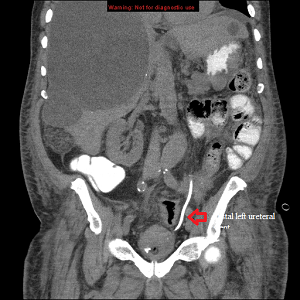

Coronal CTAP post stenting

Coronal CT abdomen and pelvis showing the distal end of the left ureteral stent in the urinary bladder.